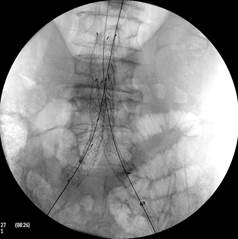

Images opératoires du 1er patient pris en charge en ambulatoire pour pose d’une endoprothèse aortique pour anévrysme de l’aorte abdominale / ©Hôpital Ambroise-Paré AP-HP

Modèle d’endoprothèse aortique utilisé dans le cadre de cette 1ère en ambulatoire